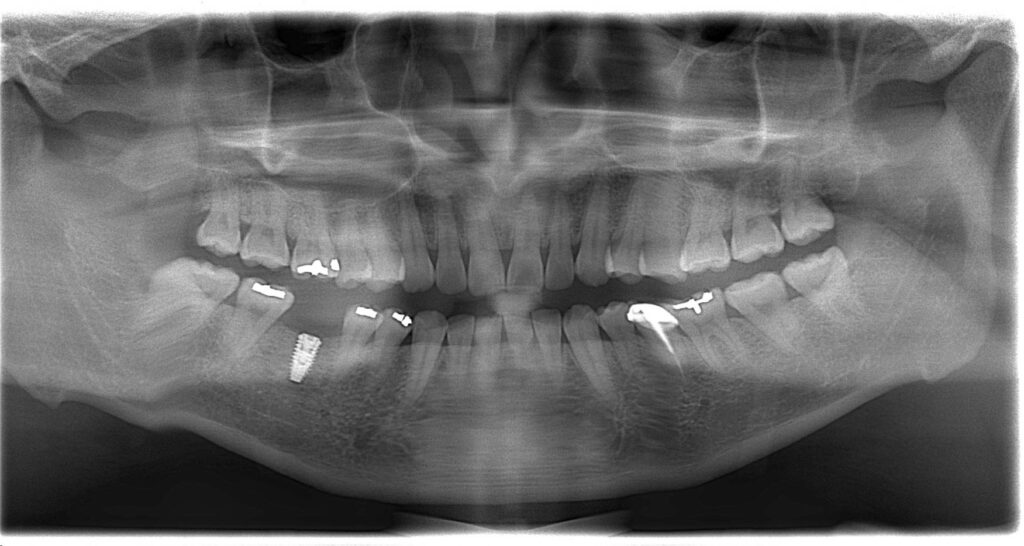

植牙後沒多久,植體出現脫落,

周圍骨頭也逐漸萎縮,

X光影像上只剩下一片明顯的黑影…

等患者再次就診時,情況已經變得更加棘手——

👉 植體已經無法維持

👉 骨頭也無法支撐新的重建

最後面對的,是一個更複雜、難度更高的缺損 💔